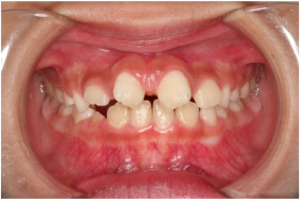

小児の隙き間を閉じる治療(小児矯正)

小児治療においてはなるべく詰め物などは使用せずに矯正治療が適応になります。